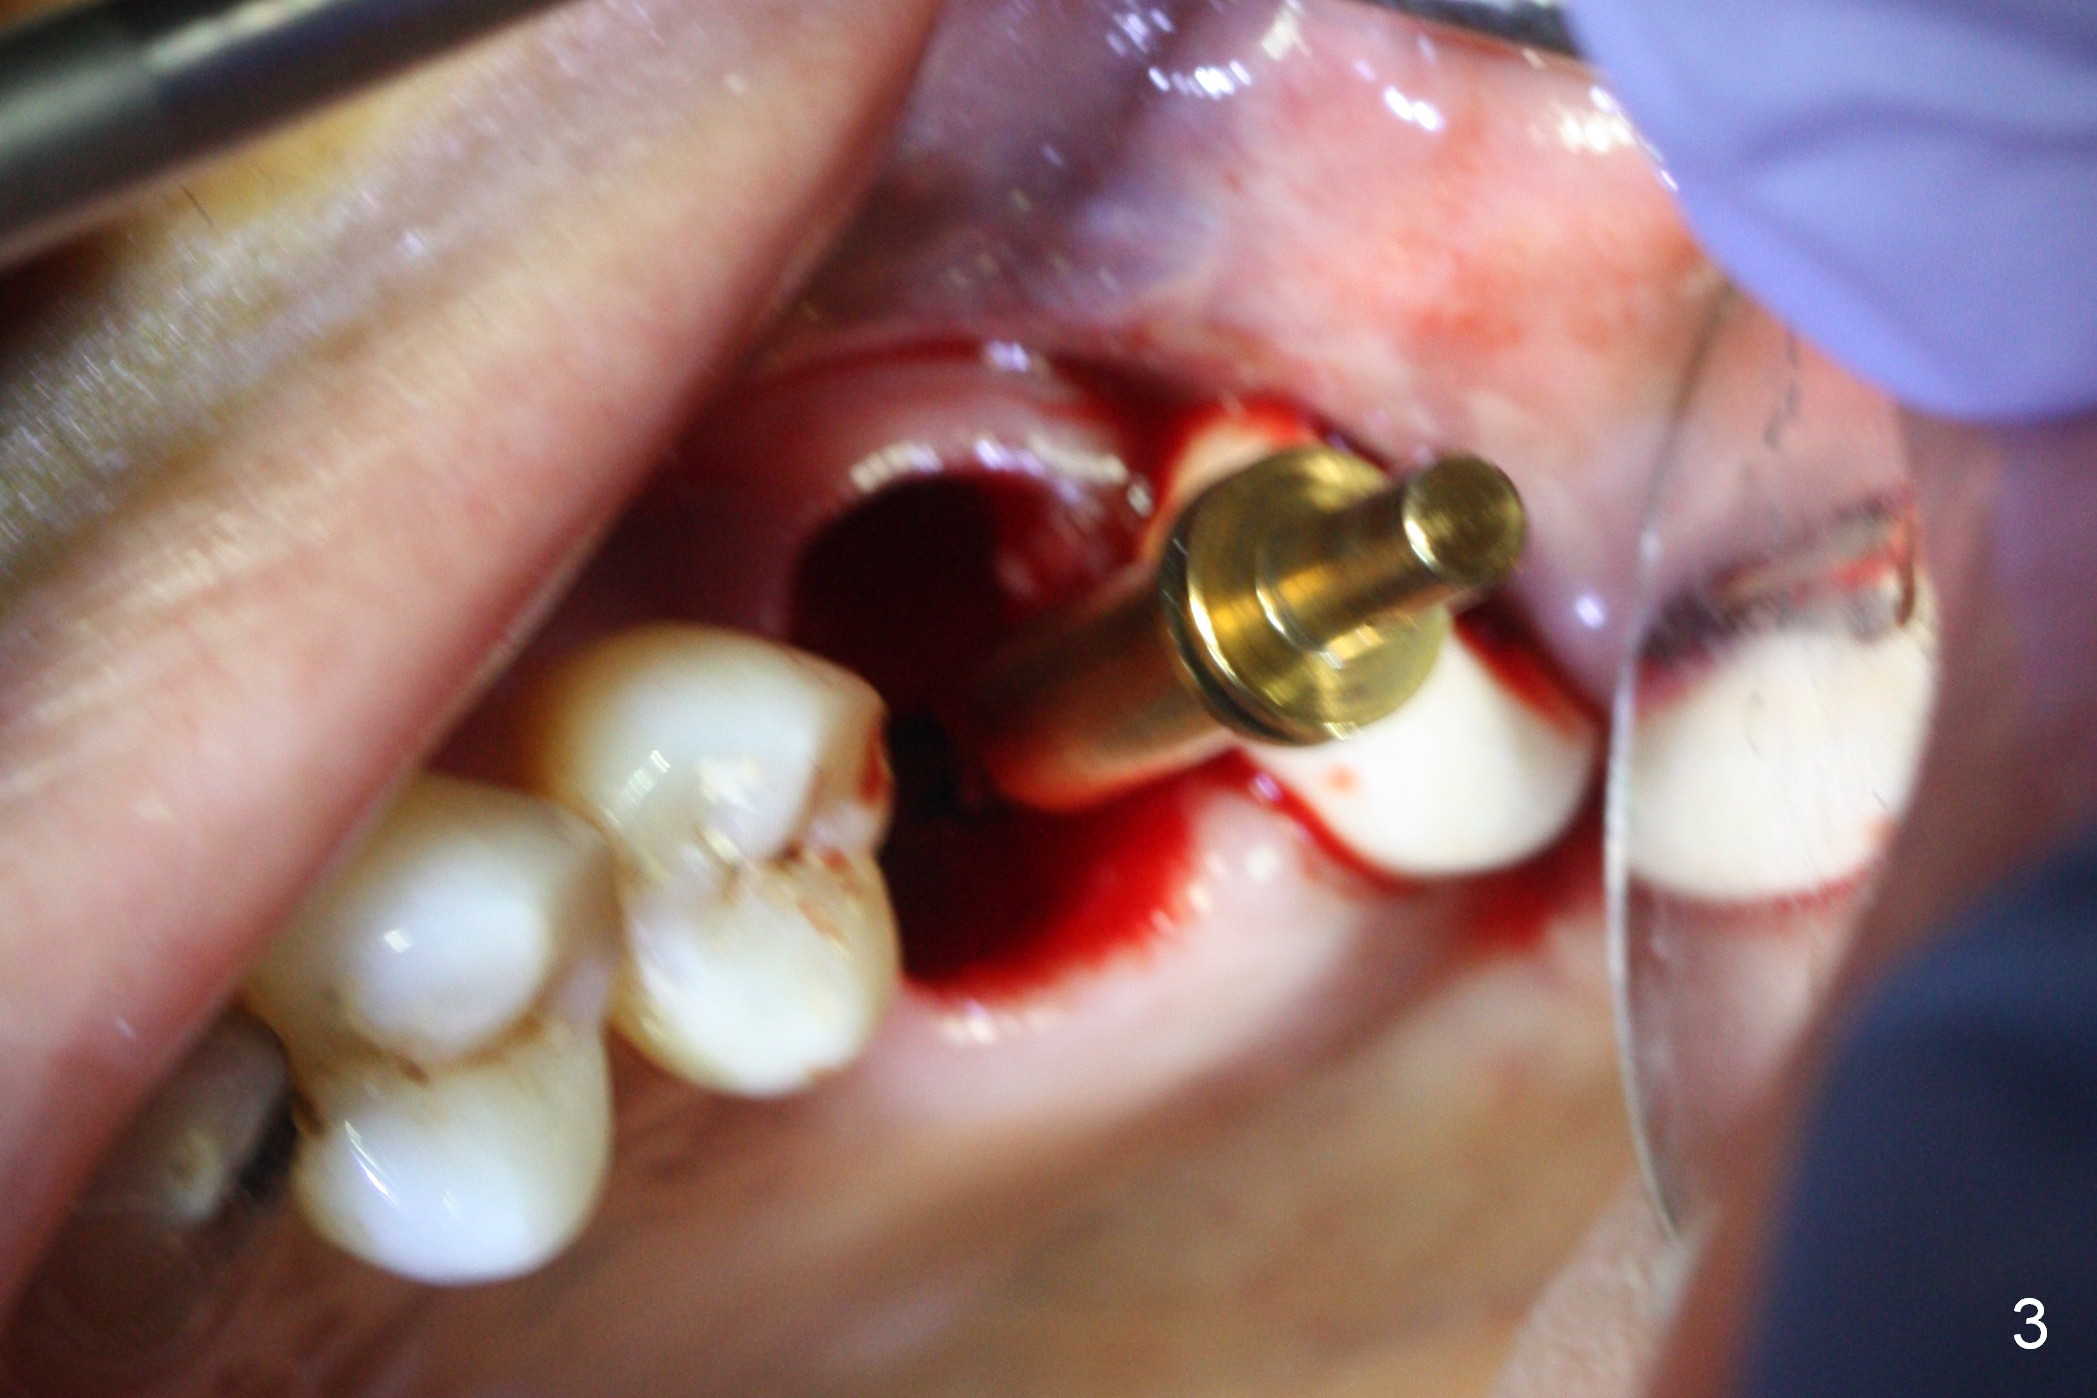

There is abundant subgingival calculus on the surfaces of the extracted tooth at #14 (Fig.1: P: palatal; MB: mesiobuccal), corresponding to the large empty socket (Fig.2 without septal bone, the buccal plate being low). Osteotomy is established palatally with Magic Expander (ME) 3.0 mm for ~ 3 mm deep (Fig.3,4) with minimal stability so that it moves during X-ray taking (Fig.4). Since the bone is dense, Magic drill 4.3 mm is used after application of ME 3.8 and 4.3 mm to complete sinus lift (Fig.5 (panoramic X-ray)). A 5x11 mm implant is placed with ~ 30 Ncm, followed by insertion of 6.5x4(3) mm Hexa abutment, bone graft and collagen membrane (Fig.6). The latter is kept in placed with an immediate provisional with clearance from the opposing dentition (Fig.7 *). Between the 1st and 3rd weeks postop, the buccal gingiva recedes with loss of bone graft (Fig.8 <) and implant thread exposure (Fig.9 * (A: abutment)). After inducing hemorrhage, allograft is placed (Fig.10 >), followed by collagen dressing (Fig.11 >). The wound closes by adding new acrylic (Fig.12 *). Thirteen days later, food is trapped in the buccal gap (Fig.13 ^). It appears that the provisional does not help wound healing. The provisional and abutment are removed; incorporating bone graft (Fig.14 *) and the implant are exposed. After placing collagen plug against the bone graft and implant, the wound is closed by periodontal dressing.